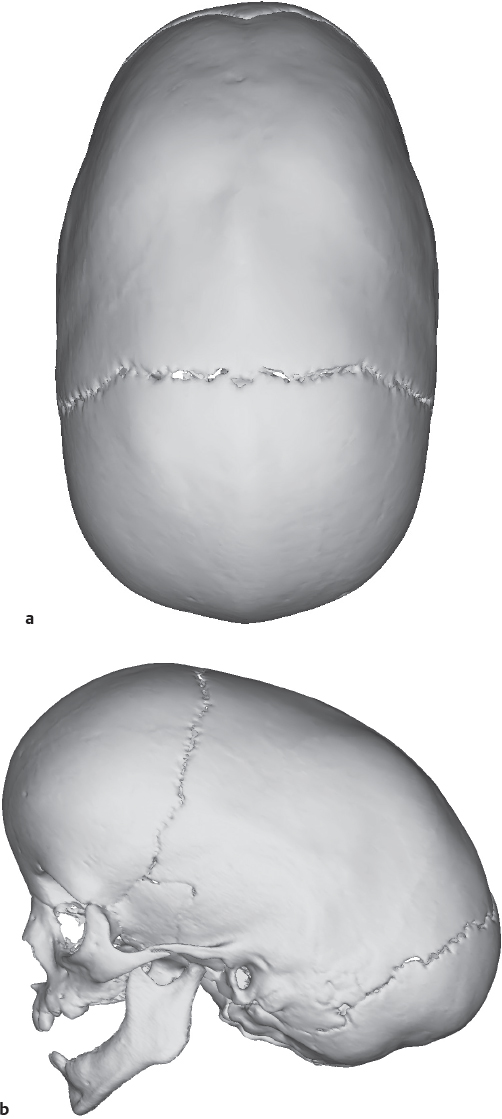

Craniomaxillofacial deformities present a range of abnormalities based on congenital conditions, trauma, and tumors. This chapter concentrates on congenital deformities, which present as a continuum from nonsynostotic deformations (posterior plagiocephaly), to single-suture synostosis, to multiple-suture craniosynostosis (craniofacial dysostosis) ( Fig. 66.1 and Table 66.1 ). Treatment of the craniosynostoses extends from conservative to multiple complex reconstructions, which may require many years; the central most basic advancement is the fronto-orbital advancement and frontal bone remodeling ( Fig. 66.2 ).

The evaluation of full-term infants with potentially misshapen heads is straightforward. 50 A long, narrow, boat-shaped head termed scaphocephaly indicates sagittal synostosis ( Fig. 66.3 ). The cephalic index is a common measure of the degree of severity in scaphocephaly. The normal cephalic index is ∼80, as measured by the cranial width over the cranial length multiplied by 100. Indexes under 71 are indicative of scaphocephaly. A top view of the typical distortion of sagittal synostosis is shown in Fig. 66.5a .

Radiologic studies are seldom needed for initial diagnosis of cranial deformities, 52 , 53 although imaging technology plays a key role in treatment decisions and preoperative planning. CT imaging and threedimensional reconstruction provide detailed information about the cranial anatomy and sutures that cannot be obtained with routine radiographs. Preoperative modeling based off of CT imaging will play an ever-increasing role in the treatment of congenital craniofacial anomalies. Computerguided planning has the potential for reduced operative times and more precise reconstructions based off of cephalometric norms. Plain films have little role in the treatment and diagnosis of children with craniosynostosis. Also, CT imaging is not without its own risks; while protocols are still being perfected to reduce radiation exposure, every effort should be made to limit the number of imaging studies. Frequently, a single threedimensional CT within a month of a reconstructive operation is recommended. If imaging studies are preformed too early during this period of significant calvarial growth, the imaging study will lose its utility as a preoperative guide. Less invasive interventions, such as endoscopic craniectomies and suturectomies, may be performed without preoperative CT scans.

The CT evaluation reveals the amount of asymmetry of the skull and the compensatory changes that have occurred; in addition, it allows for identification of the venous sinuses. 54 , 55 The largest risk factor in these operations is blood loss and a clear knowledge of the position of the torcula helps prevent inadvertent injury in low posterior remodeling procedures. The CT scan in occipital deformities may also indicate abnormalities of the brain and the bone. Infants with severe deformities typically show diminished posterior subarachnoid fluid similar to the changes seen with increased ICP, but on a more localized basis. This appears to extend into the ventricular system, resulting in ventricular effacement. Generalized subarachnoid space dilation per se anteriorly does not indicate neurologic impairment, for it frequently is found in posterior plagiocephaly with normal neurologic status. With severe compression, sometimes the ipsilateral perimesencephalic cistern is effaced also. The finding usually correlates with an irregular, patchy, diminished thickness of the occipital bone. The patchiness is greatest in bilateral cases and appears to be similar to the copper-beaten or thumbprinting appearance seen on plain radiographs. “Copper beating” may not be a good marker for raised ICP because it occurs late and is an inconsistent finding. 56